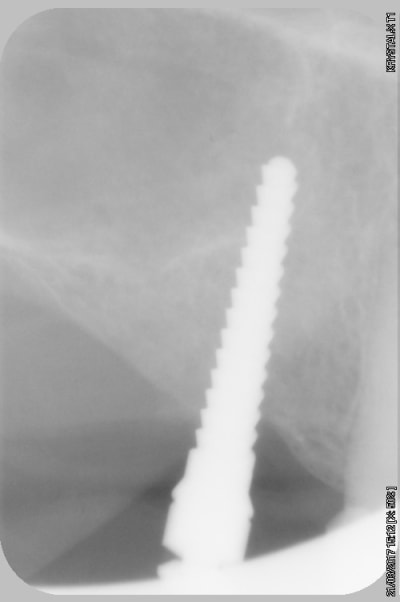

par contre je fais pas mal de radios, exemple spreaders trop près de la racine donc changement d'axe (d'où l’intérêt de l'expansion)